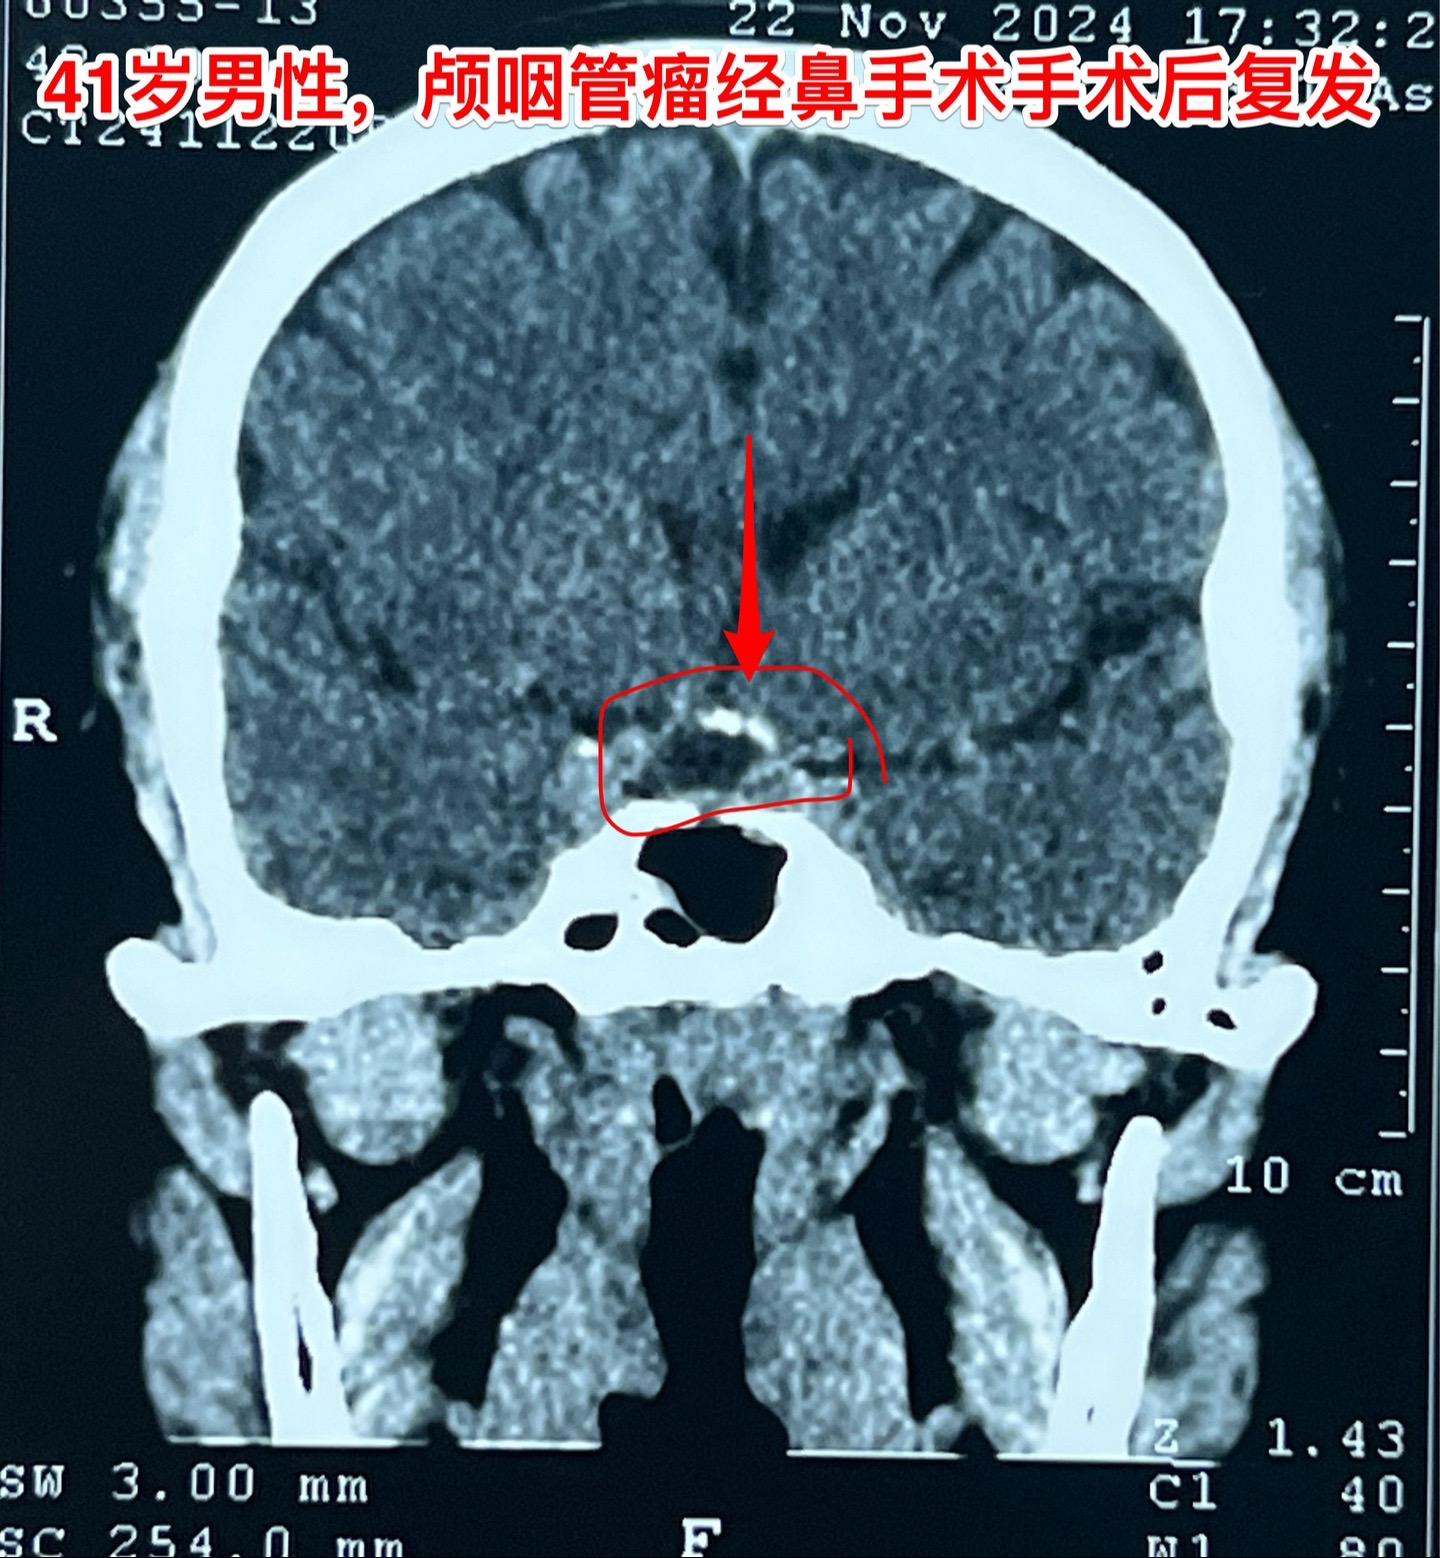

又一个经鼻手术后复发的颅咽管瘤。41岁的大连市男性,三年前因视力下降在辽宁省作了经鼻手术切除颅咽管瘤。手术后视力好转了,当时术后三个月复查磁共振显示肿瘤有残留。随后观察,多次复查磁共振显示肿瘤体积在增大,而且再次出现视力下降。如图所示,肿瘤有钙化,是典型的造釉性颅咽管瘤,一部分肿瘤位于鞍背后方,手术切除肿瘤还是有难度的。 2024年11月来找我办理住院手续,11月29日作了开颅手术(十一月的最后一个手术)。